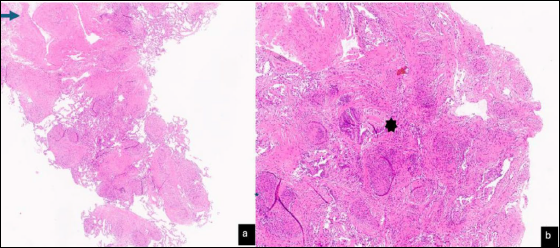

L’analisi morfologica delle criobiopsie polmonari (Fig. 2 a-b) dimostra la presenza di granulomi non necrotizzanti su un background di fibrosi jalina, più evidente in sede sub pleurica. Si evidenzia inoltre obliterazione bronchiolare determinata dagli stessi granulomi e in parte da un quadro di bronchiolite cicatriziale.

Figura 2.Criobiopsia polmonare transbronchiale: (a) granulomi non necrotizzanti in background di fibrosi jalina con evidente ispessimento subpleurico (➙) - Ematossilina Eosina x 2; (b) granulomi non necrotizzanti che determinano la parziale obliterazione del lume di un bronchiolo. È presente anche fibrosi subepiteliale (bronchiolite costrittiva) (✱) - Ematossilina Eosina x10.